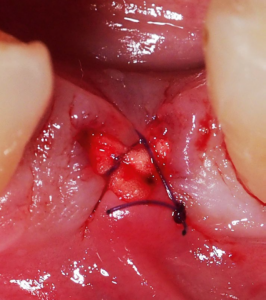

Wound edge approximation with RESOLON® ORAL 6/0 with ART 13mm

Wound edge approximation with RESOLON® ORAL 6/0 with ART 13mm BYRESORBA Wound edge approximation with RESOLON® ORAL 6/0 with ART 13mm black needle לפרטים נוספים